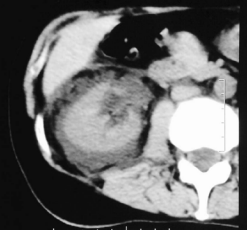

She received symptomatic treatment in hospital. In urinary ultrasonography, hydronephrosis grade II and abundant fluid collection in perinephric area was seen. The abdominal computed tomography (CT) confirmed the finding (Figure 1).

Figure 1 Abdominal CT. Abundant fluid collection in perinephric area and hydronephrosis grade II.